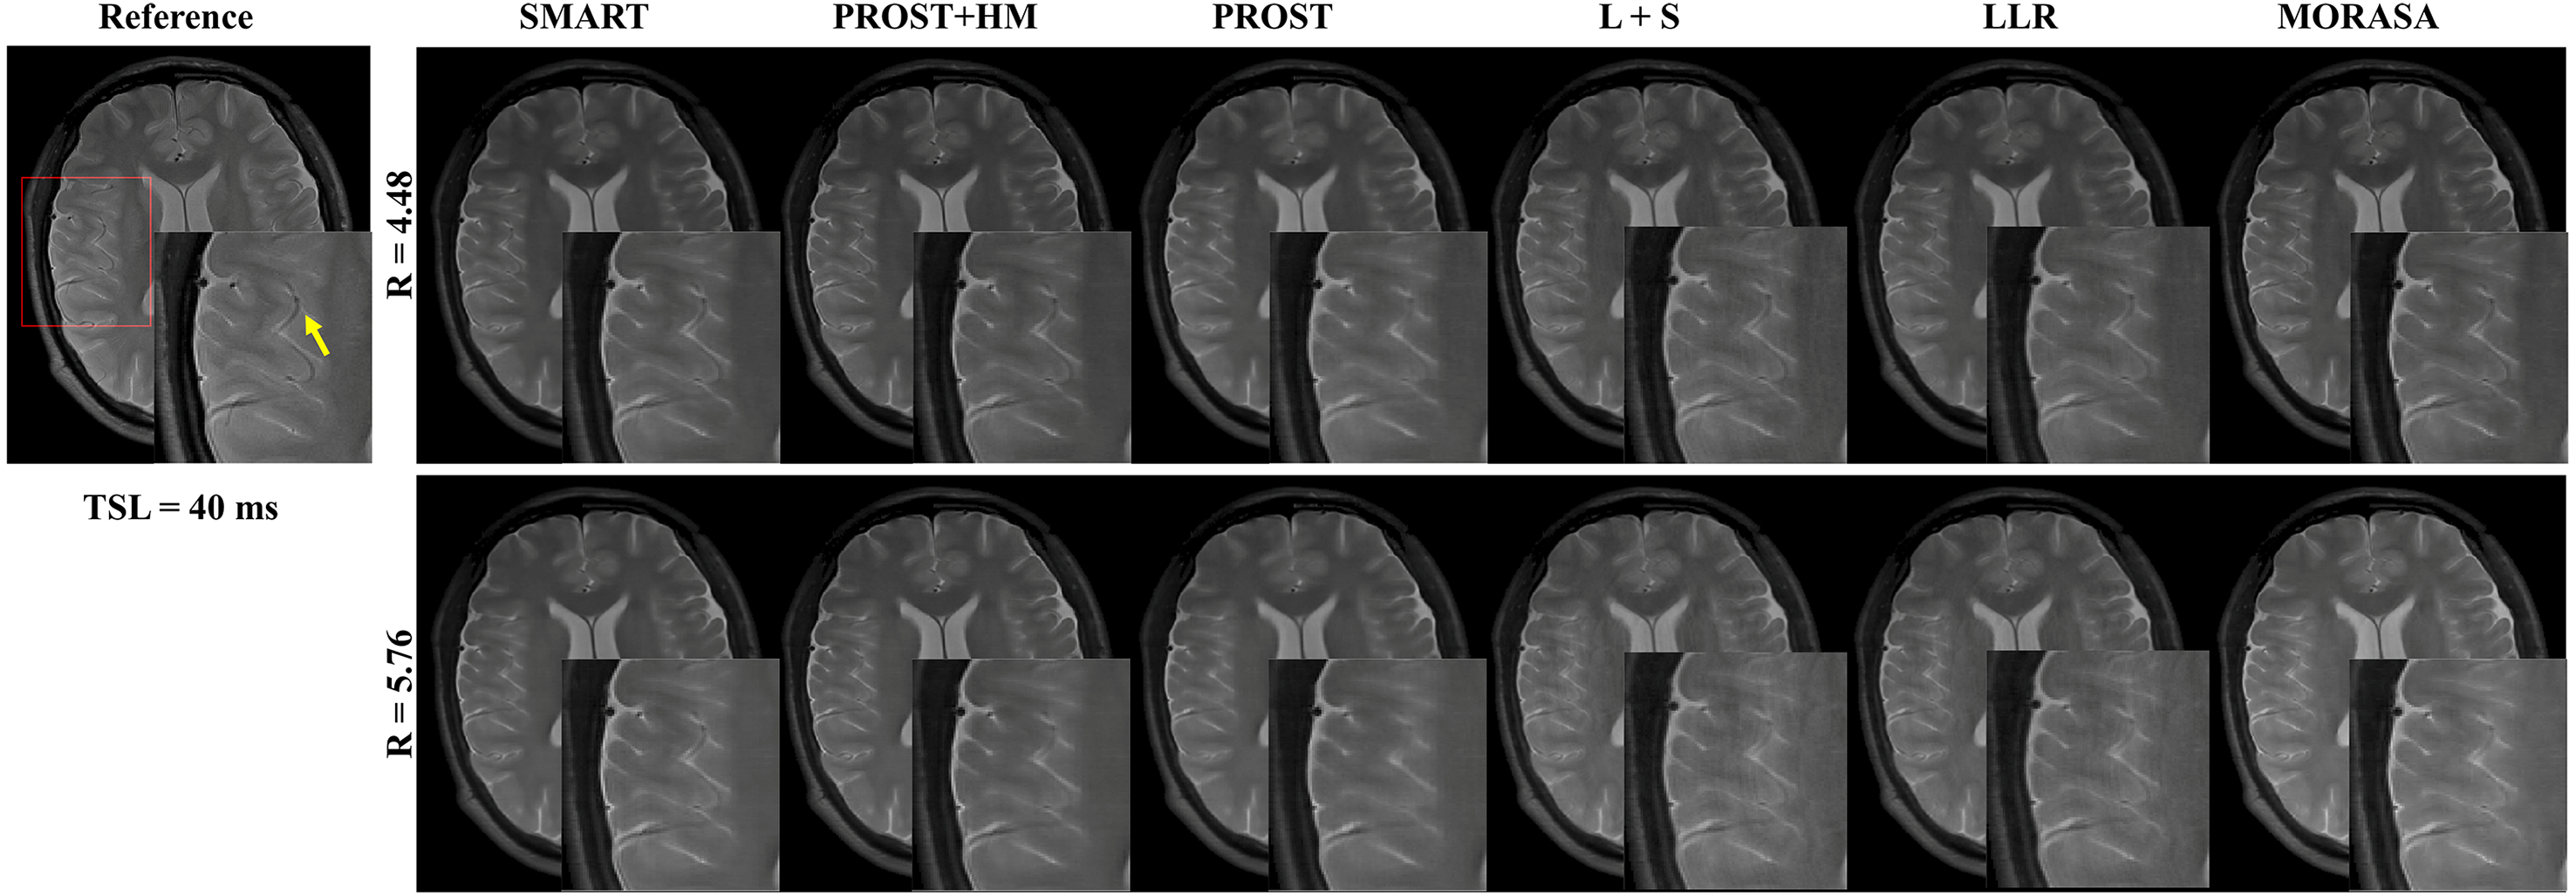

Fig. 6 shows the prospective reconstructed -weighted images (at TSL = 40 ms) from another volunteer and the magnified images using the SMART, PROST + HM, PROST, L + S, LLR, and MORASA methods. Visual artifacts can be observed in the magnified images of reconstructions at all accelerating factors using the L + S and LLR methods. The images reconstructed using the PROST + HM and PROST methods were blurred compared to those reconstructed using the SMART method. Some image details (namely, the blood vessel marked in a yellow arrow) can narrowly be seen in the reconstructions using the PROST + HM and MORASA methods and disappeared in the reconstruction using the PROST method at R = 5.76. In contrast, the image details were well preserved using the SMART method. The maps reconstructed using the methods above are shown in supplementary information Fig. S4. Similar conclusions can be drawn from the maps.

Supplementary information Fig. S4 shows the corresponding maps reconstructed using the SMART, PROST + HM, PROST, L + S, LLR, and MORASA methods and the error maps between the reconstructed map and the reference map. The maps reconstructed using the SMART method exhibited superior reconstruction performance compared to those reconstructed using the other four methods, with the smallest nRMSEs and error maps for both acceleration factors.